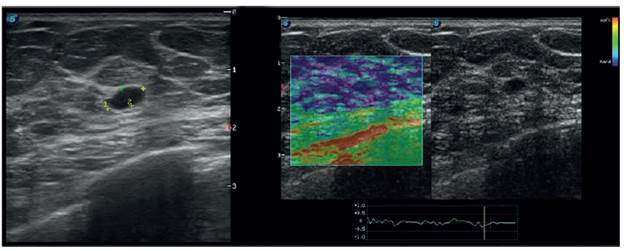

En 2018, presentó lesión mamaria palpable que motivó su consulta. En la mamografía se evidenció un nódulo isodenso en el tercio posterior del cuadrante superior externo de la mama derecha, y en la mama izquierda se observaron cambios postquirúrgicos debido al antecedente descrito (figuras 1 y 2). Se consideró BI-RADS 0 en la mamografía, por lo que se realizó una ecografía mamaria en la que se delimitó un nódulo hipoecoico de 6,8 x 3,5 mm, ubicado en el cuadrante superior externo de la mama derecha; lesión bien definida con eje mayor paralelo a la piel, sin efecto acústico posterior, sin señal Doppler color y de consistencia dura a la elastografía (figura 3), con aspecto imaginológico probablemente benigno, por lo que se consideró un BI-RADS 3 ecográfico, y se procedió a realizar una biopsia por trucut.